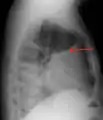

A pleural effusion appears as an area of whiteness on a standard posteroanterior chest X-ray.[12] Normally, the space between the visceral pleura and the parietal pleura cannot be seen. A pleural effusion infiltrates the space between these layers. Because the pleural effusion has a density similar to water, it can be seen on radiographs. Since the effusion has greater density than the rest of the lung, it gravitates towards the lower portions of the pleural cavity. The pleural effusion behaves according to basic fluid dynamics, conforming to the shape of pleural space, which is determined by the lung and chest wall. If the pleural space contains both air and fluid, then an air-fluid level that is horizontal will be present, instead of conforming to the lung space.[13] Chest radiographs in the lateral decubitus position (with the patient lying on the side of the pleural effusion) are more sensitive and can detect as little as 50 mL of fluid. Between 250 and 600mL of fluid must be present before upright chest X-rays can detect a pleural effusion (e.g., blunted costophrenic angles).[14]

A pleural effusion as seen on lateral upright chest x-ray- Pleural effusion as seen behind the heart.[17]

Massive pleural effusion, later proven to be hemothorax in a South Indian male.